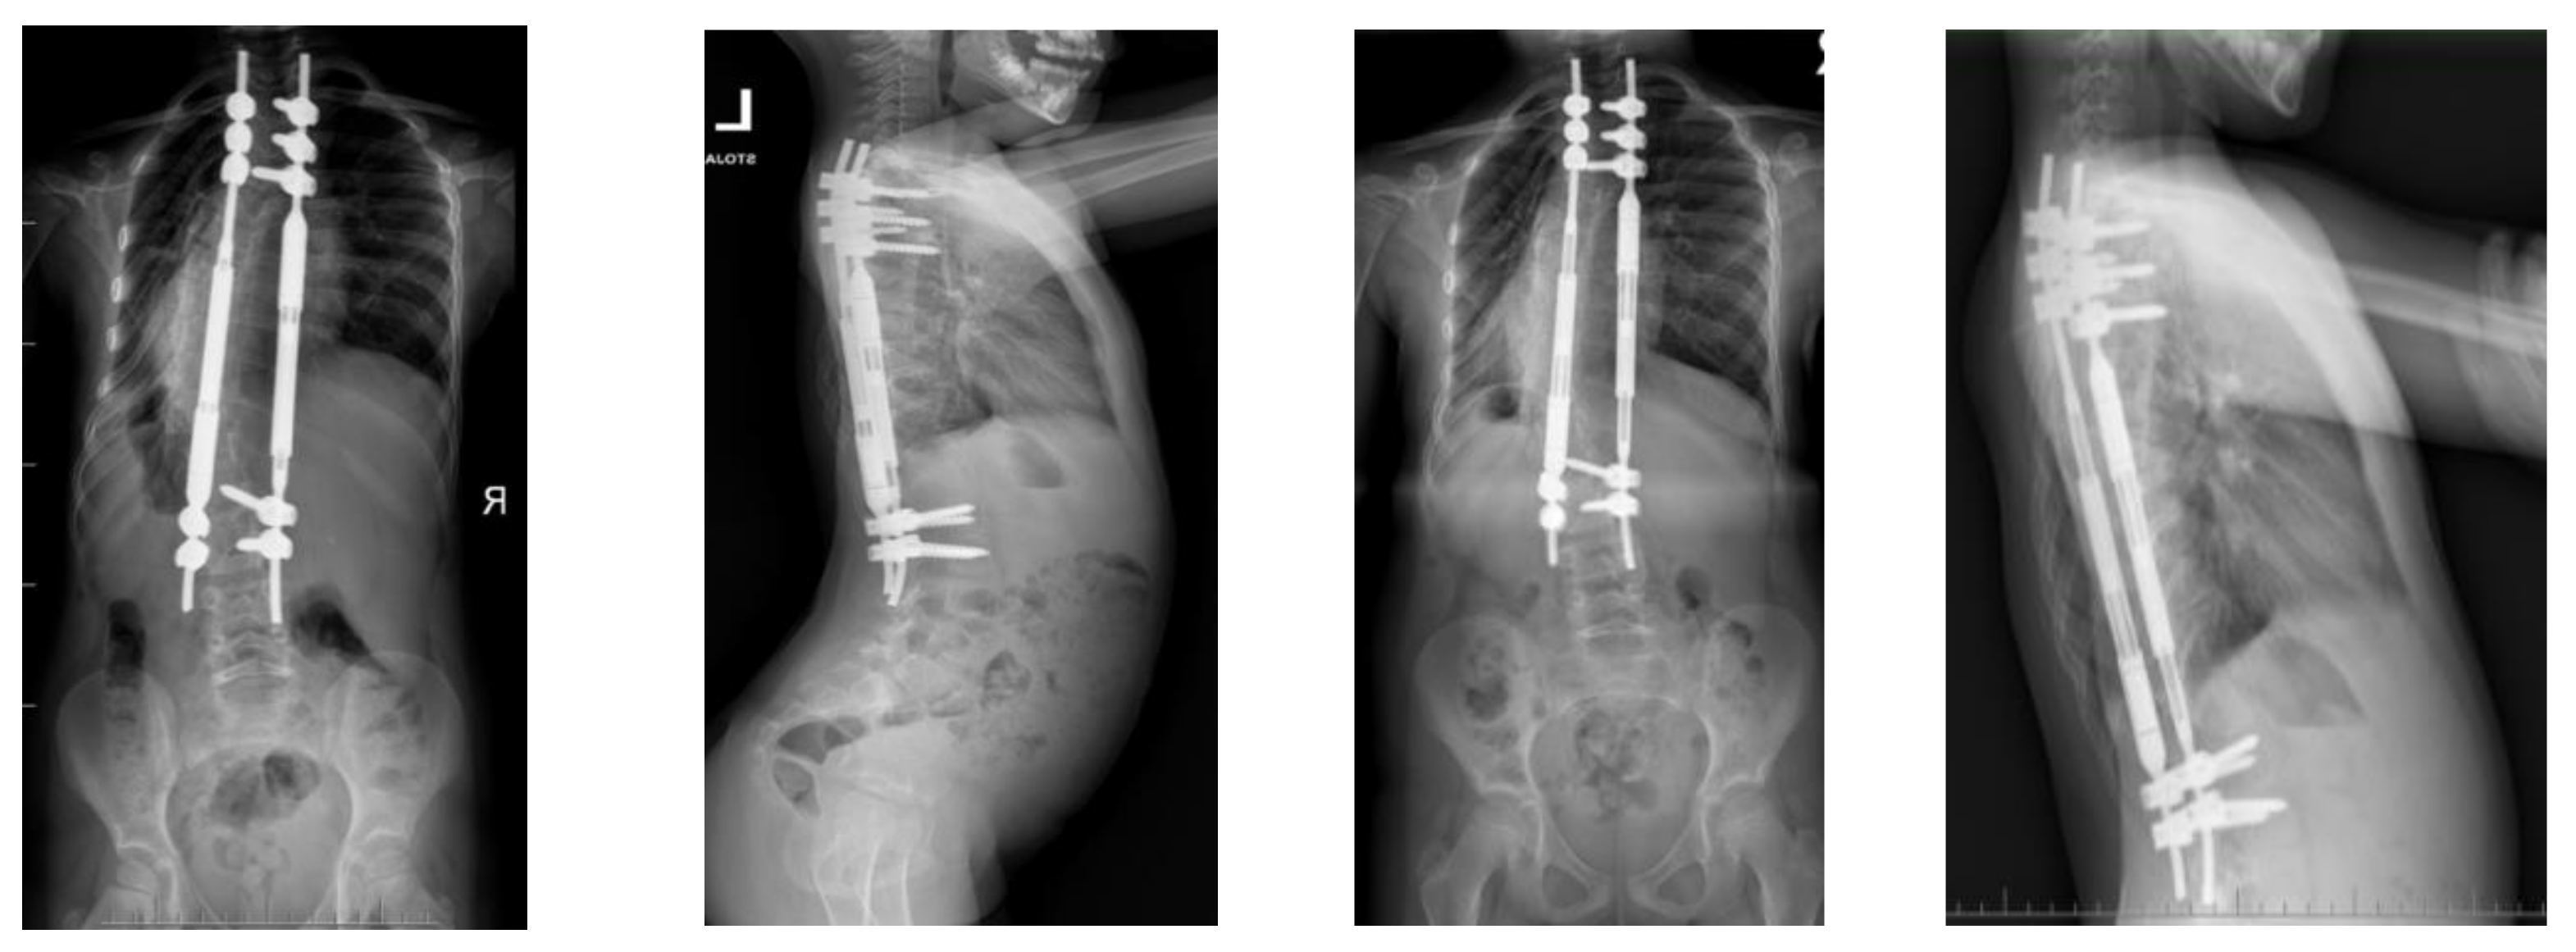

No deep infections were observed during follow-up. At follow-up after 4.5 years, we observed a loss of distraction without other known radiological signs mentioned in the literature (Figure 7).

Figure 7.

X-rays at follow-up after 1 year (left AP and LAT) and at follow-up after 4.5 years (right AP and LAT) before revision surgery for MCGR replacement.

We decided to replace the 4.5 MCGR with a 5.5 MCGR. We performed revision surgery to replace the screws and MCGRs in January 2022 (Figure 8).

Figure 8.

X-rays at 5-year follow-up, after revision surgery for MCGR replacement.